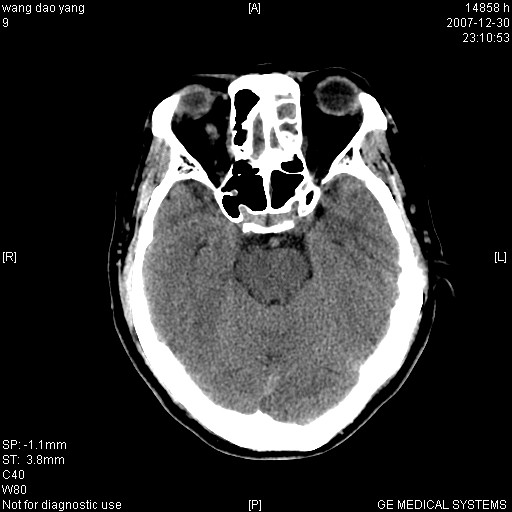

因外伤做ct

1。左侧筛窦蝶窦少量积液,2。右眼眶视神经鞘瘤可能性大,建议增强一下

肌圆锥内占位性病变,血管瘤可能性大。

1 病灶位于肌圆锥内,从第一帧看,和视神经关系不紧密。

2 病灶边界光整,形态欠规则。

3 病灶密度明显高于同层面的正常软组织。

外伤的话首先考虑球后血肿!!

肌圆锥内类软组织密度影,边缘清楚,位于视神经上方,考虑:炎性假瘤可能性大.

建议:强化扫描.

病灶形态不规则,临床有外伤史,支持考虑:球后血肿!!!

考虑右侧视神经脑膜瘤或血管瘤,建议增强进一步检查。

考虑右侧视神经脑膜瘤或视神经胶质瘤,建议增强进一步检查鉴别。

考虑右侧视神经鞘瘤,脑膜瘤或纤维瘤。

球后肌锥内小团块状软组织密度影(性质待定);建议:行ct增强扫描或mri检查。